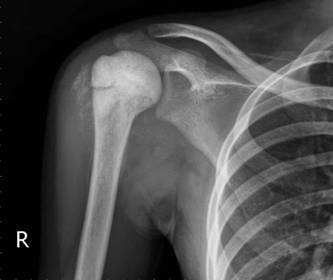

【113-1 醫學(五) 第48題】承上題,檢查全身無明顯出血及外傷,頭部電腦斷層無頭骨骨折及顱內出血,但仍意識不清,胸腹部X 光如圖所示,輸注packed RBC 100 mL 後量測生命徵象,血壓114/53 mmHg,心跳163/min,呼吸28/min,體溫 36.7℃,脈搏血氧飽和度90%,下列敘述何者錯誤?

這張胸腹部X光片顯示右側胸腔有明顯的積液,在創傷病患合併休克的臨床情境下,高度懷疑是血胸。因此,選項C中「右側可能血胸」的說法,因為其確定性不足,反而成為錯誤的敘述。